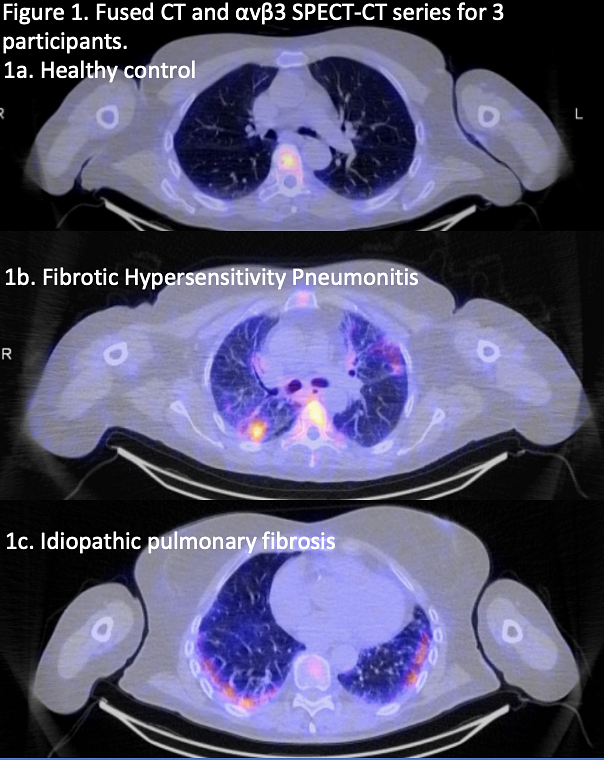

When injected into a patient, 99mTc-maraciclatide circulates through the body and accumulates in areas of the lung where inflammation is active. A subsequent SPECT-CT scan, which combines functional nuclear imaging with anatomical CT imaging, can then generate a detailed 3D map pinpointing the precise location and extent of this inflammatory activity. Preliminary data from the company's Phase II PREDICT-ILD trial have already demonstrated that visualizing inflammation in people with fibrotic-ILD could be feasible with this method. Full results from the trial are expected to be published later this year.